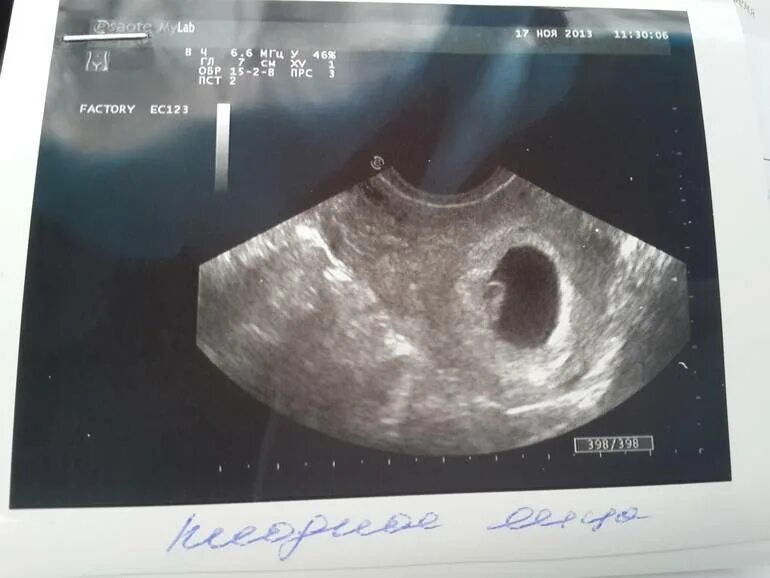

Не видно эмбриона на 6 неделе беременности